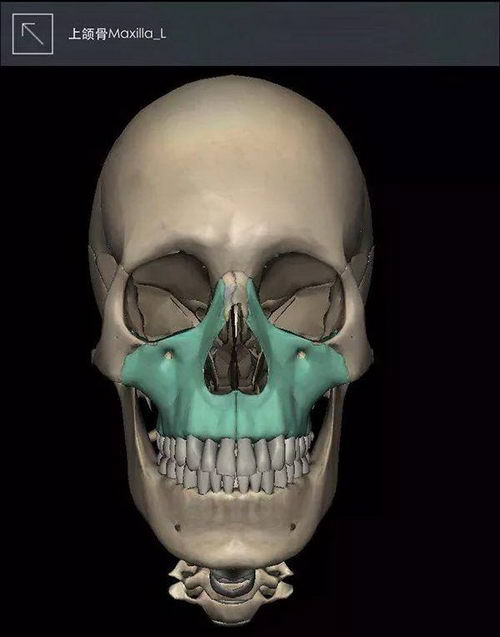

很多小时候很漂亮的女生,长大后就颜值下线了,多半是因为凸嘴和龅牙,有凸嘴龅牙的女生都不会太美。我们先弄明白一个送分题:什么是双鄂?

双鄂=上颚(上颌骨)+下颚(下颌骨)

(图中带颜色部位)

▲图片来自《3Dbody》